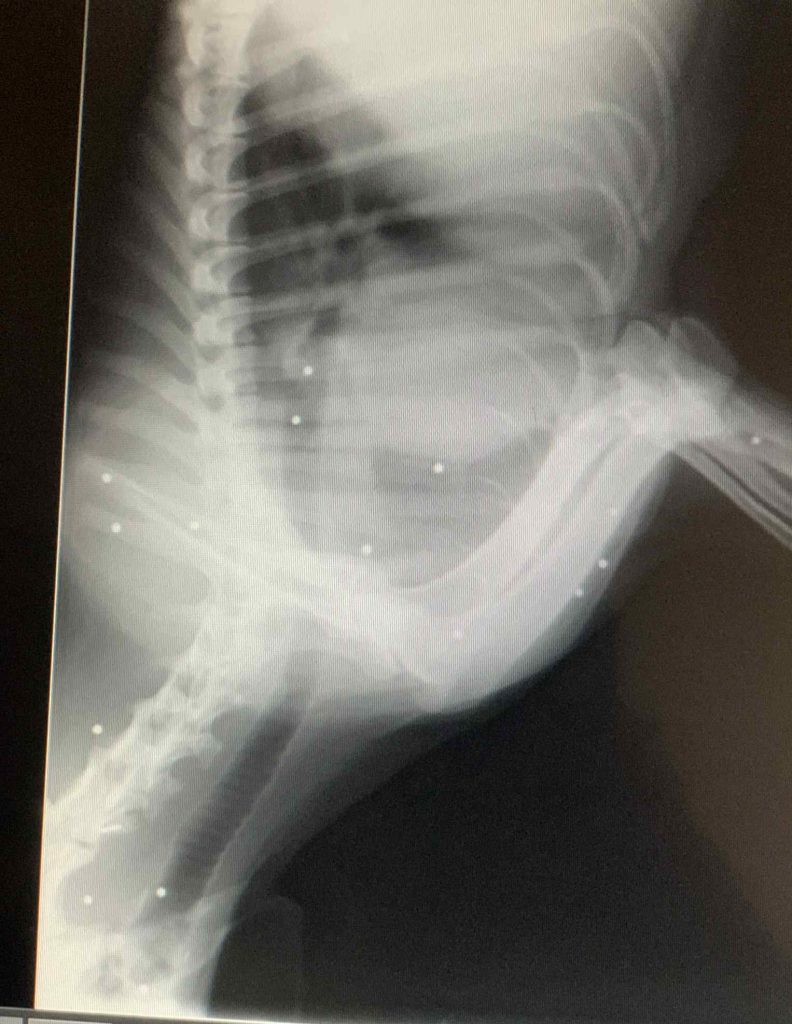

Η μητέρα μεταφέρθηκε σε ασφαλές περιβάλλον, όμως οι ακτινογραφίες αποκάλυψαν κάτι ανατριχιαστικό: το σώμα της είναι γεμάτο σκάγια, σημάδι ότι είχε δεχθεί πυροβολισμούς στο παρελθόν και, παρά τα τραύματα, κατάφερε να επιβιώσει.